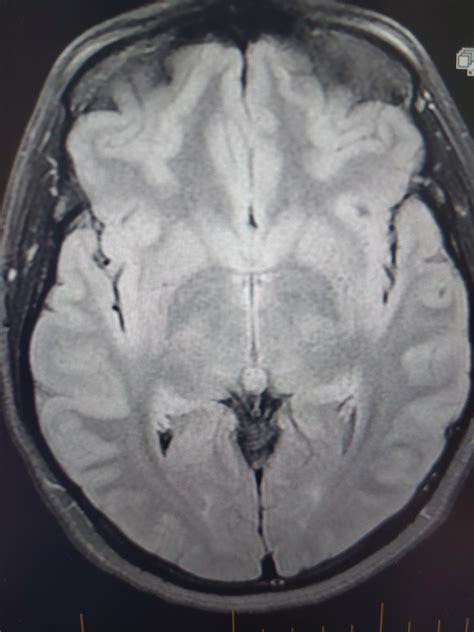

Brain acne! Two symptomatic brain cysts (Rathke's Cleft and pineal) : r/Radiology

Are you experiencing unexplained headaches or vision changes? Discover the most common pineal cyst symptoms, including neurological issues and intracranial pressure signs. Learn when these fluid-filled brain lesions require medical imaging like an MRI and explore available treatment options to manage potential complications. Understand your diagnosis and regain peace of mind with our expert guide to pineal gland health.